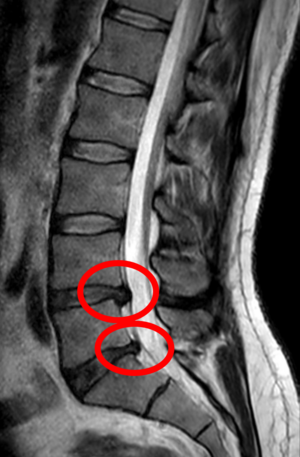

انزلاق غضروفي خلال تمزق في الحلقة (موضح بالتصوير بالرنين المغناطيسي).[9]

- التصوير بالرنين المغناطيسي هي الدراسة المعيارية الذهبية لتأكيد الاشتباه في انزلاق غضروفي. مع دقة تشخيصية تبلغ 97%، فهي الدراسة الأكثر حساسية لتصور الانزلاق الغضروفي بسبب قدرتها الكبيرة على تصور الأنسجة الرخوة. كما يتمتع التصوير بالرنين المغناطيسي بموثوقية أعلى بين المراقبين مقارنة بوسائل التصوير الأخرى. ويشير إلى انزلاق غضروفي عندما يظهر إشارة متزايدة مرجحة بـ T2 عند المنطقة الخلفية التي تغطي 10% من القرص. وقد أظهرت أمراض الانزلاق الغضروفي ارتباطًا بتغيرات النوع 1 من مقياس موديك. عند تقييم اعتلالات الجذور العصبية القطنية بعد الجراحة، فإن التوصية هي إجراء التصوير بالرنين المغناطيسي مع التباين ما لم يكن هناك موانع أخرى. يعد التصوير بالرنين المغناطيسي أكثر فعالية من التصوير المقطعي المحوسب في التمييز بين الأسباب الالتهابية أو الخبيثة للانزلاق الغضروفي. يُشار إليه في وقت مبكر نسبيًا في مسار التقييم (<8 أسابيع) عندما يظهر المريض مؤشرات نسبية مثل الألم الشديد والعجز الحركي العصبي ومتلازمة ذيل الفرس. التصوير الموتر الانتشاري هو نوع من تسلسل التصوير بالرنين المغناطيسي المستخدم للكشف عن التغيرات الدقيقة في جذر العصب. قد يكون مفيدًا في فهم التغييرات التي تحدث بعد أن يضغط القرص القطني المنفتق على جذر العصب، وقد يساعد في التمييز بين المرضى الذين يحتاجون إلى تدخل جراحي. في المرضى الذين لديهم شكوك عالية في اعتلال الجذور العصبية بسبب الانزلاق الغضروفي القطني، ومع ذلك فإن التصوير بالرنين المغناطيسي غامض أو سلبي، يوصى بدراسات التوصيل العصبي.[44] توفر الصور المرجحة الناتجة عن التصوير بالرنين المغناطيسي (T2) تصور واضح لمادة القرص البارز في القناة الشوكية.